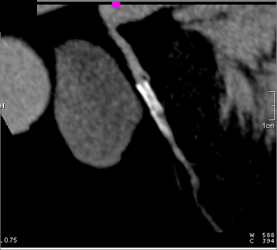

Diseased RCA